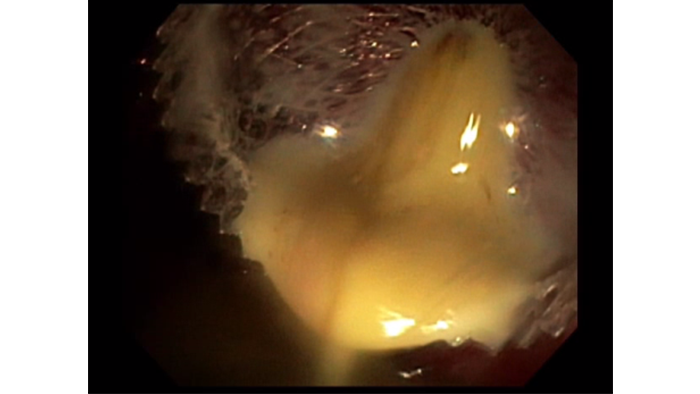

4. Pancreatic fluid collection drainage​

Approximately 1L of purulent content, mixed with solid and liquid PFC drained from the WON to the stomach. The stent was left in situ.​

The larger 20mm AXIOS™ Stent was ideal for this patient as it allowed rapid drainage of both solid and liquid contents and will greatly facilitate endoscopic necrosectomy if needed in the future.​